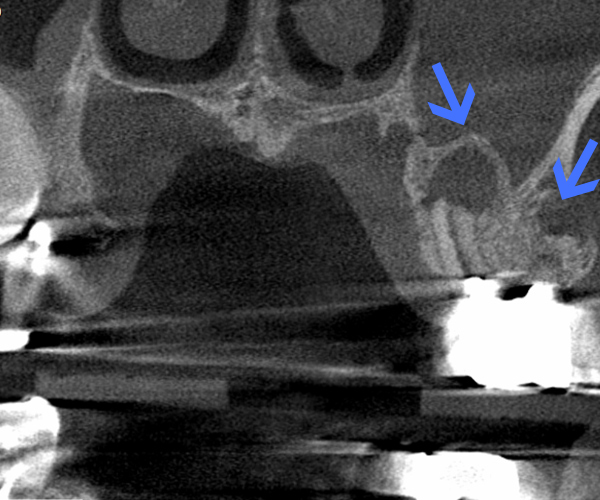

Before

歯性上顎洞炎(副鼻腔炎)

根尖病巣により洞底膜がラッパ状に開いている。

After

6ヶ月後のCT

洞底膜はきれいに再生され病巣は消失しております。